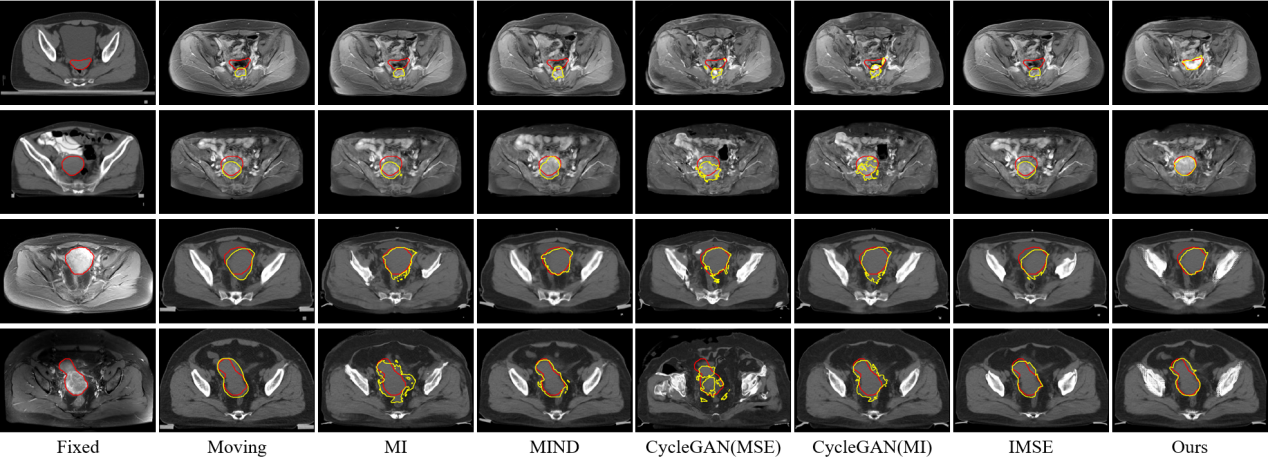

研究结果表明,SynMSE 在L2R 2022 CT-MR腹部数据集、临床宫颈CT-MR数据集以及CuRIOUS MR-US脑数据集上均取得了最优配准性能。与传统方法相比,SynMSE显著提升了Dice系数、降低了HD95与TRE误差,实现了在复杂模态差异下的高精度解剖结构对齐。图4-图6分别为所提出方法在三个数据集上的定性结果展示,红色标注代表固定图像的目标器官区域,黄色标注代表浮动图像与配准后图像的目标器官区域。表示图中结果显示,SynMSE更好的克服了多模态图像间的复杂分布差异,不仅实现了更精确的配准效果,而且有效保持了组织边界与解剖拓扑的完整性,明显优于现有方法。

图5:所提出方法与现有方法在临床宫颈CT-MR数据集上的定性效果